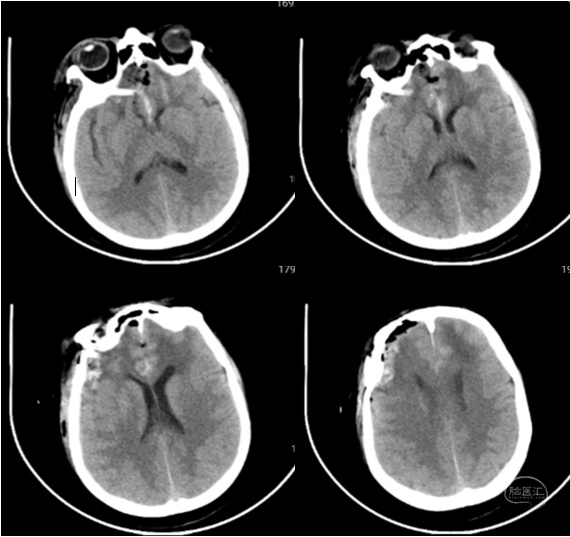

注:术后第一天CT显示额叶脑挫伤及水肿不重

手术前后比较:前颅底增生骨质处理情况

注:术后CT骨窗及三维重建